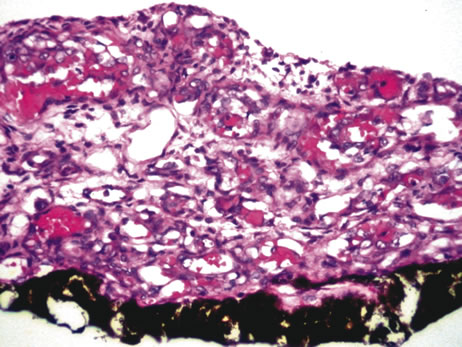

Diffuse granulomatous inflammation is typically seen in sympathetic ophthalmia and Vogt-Koyanagi-Harada (VKH) disease. Sympathetic ophthalmia has classically been described as an intraocular inflammatory response in the non-traumatized fellow eye following penetrating injury to the contralateral eye. The disorder is characterized by waxing and waning episodes of chronic inflammation; untreated, it may lead to blindness in both eyes. The patient may present with mild pain, photophobia, and vision loss. The exciting eye (previously traumatized) may demonstrate decreased vision and increased photophobia. Both eyes may reveal ciliary injection and vitritis.The exciting eye may develop keratic precipitates. The sympathizing eye may demonstrate mild uveitis and KPs on the endothelium. Posterior segment findings include papillitis, Dalen-Fuchs nodules (yellow-white lesions beneath the RPE), choroidal granulomas, and exudative retinal detachments. Histologically, both the traumatized and sympathizing eyes show diffuse granulomatous inflammation made up of nests of epithelioid cells and giant cells mixed with lymphocytes. This inflammation does not extend to involve the choriocapillaris. Dalen-Fuchs nodules are composed of nodular clusters of epithelioid cells lying between the RPE and Bruch's membrane (Fig. 22). Sympathetic ophthalmia represents an autoimmune process that may be related to an altered T-cell response to uveal antigens or other intraocular proteins.120–124

Fig. 22. Sympathetic ophthalmia. Dalen-Fuchs nodule is composed of clusters of epithelioid cells lying between Bruch's membrane and the retinal pigment epithelium. (Hemotoxylin-eosin ×140.)